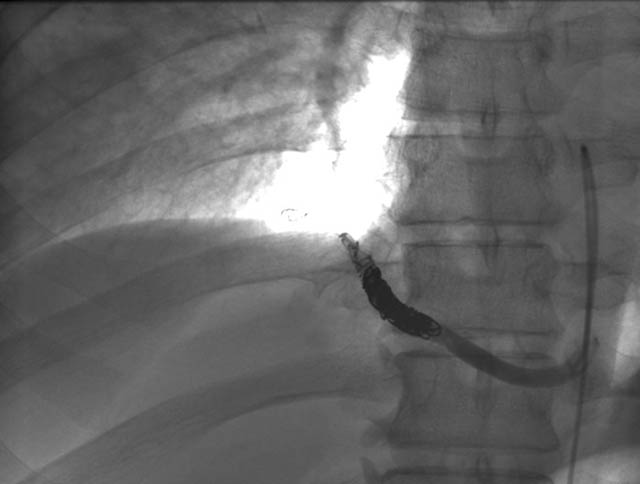

A previously healthy 43-year-old male presented with cough, fevers, and leukocytosis. A chest radiograph (Figure 1) revealed extensive consolidation in the right lower lung containing multiple cavities with air-fluid levels consistent with a necrotizing infection. A chest computed tomogram (Figure 2) showed an abscess cavity and consolidation in the right lower lobe with an aberrant blood supply from the descending aorta. This systemic blood supply was confirmed by subsequent 3D reconstruction (Figure 3). He was initially treated with IV antibiotics, resulting in normalization of his temperature and white blood cell count. He was then discharged home on a 3-week course of oral antibiotics. Three days prior to a planned surgical resection, he underwent angiographic localization of the feeding artery (Figure 4) and coil embolization (Figure 5).

To prevent complications from infection, hemorrhage, and possible malignancy, surgical resection of ILS is recommended [7]. Preoperative coil embolization of the arterial supply can decrease the risk of hemorrhagic complications and has been reported in the pediatric literature as an alternative to surgery [8]. However, intraoperative vascular control of this vessel may be more difficult if the coils are positioned in the artery outside of the sequestration rather than within the sequestration. Operative approaches involving thoracoscopy and thoracotomy have been reported, utilizing lobectomy, sequestrectomy, and wedge resection [9]. A recent review found pediatric and adult ILS anatomy, presentation, and treatment options to be similar [10].